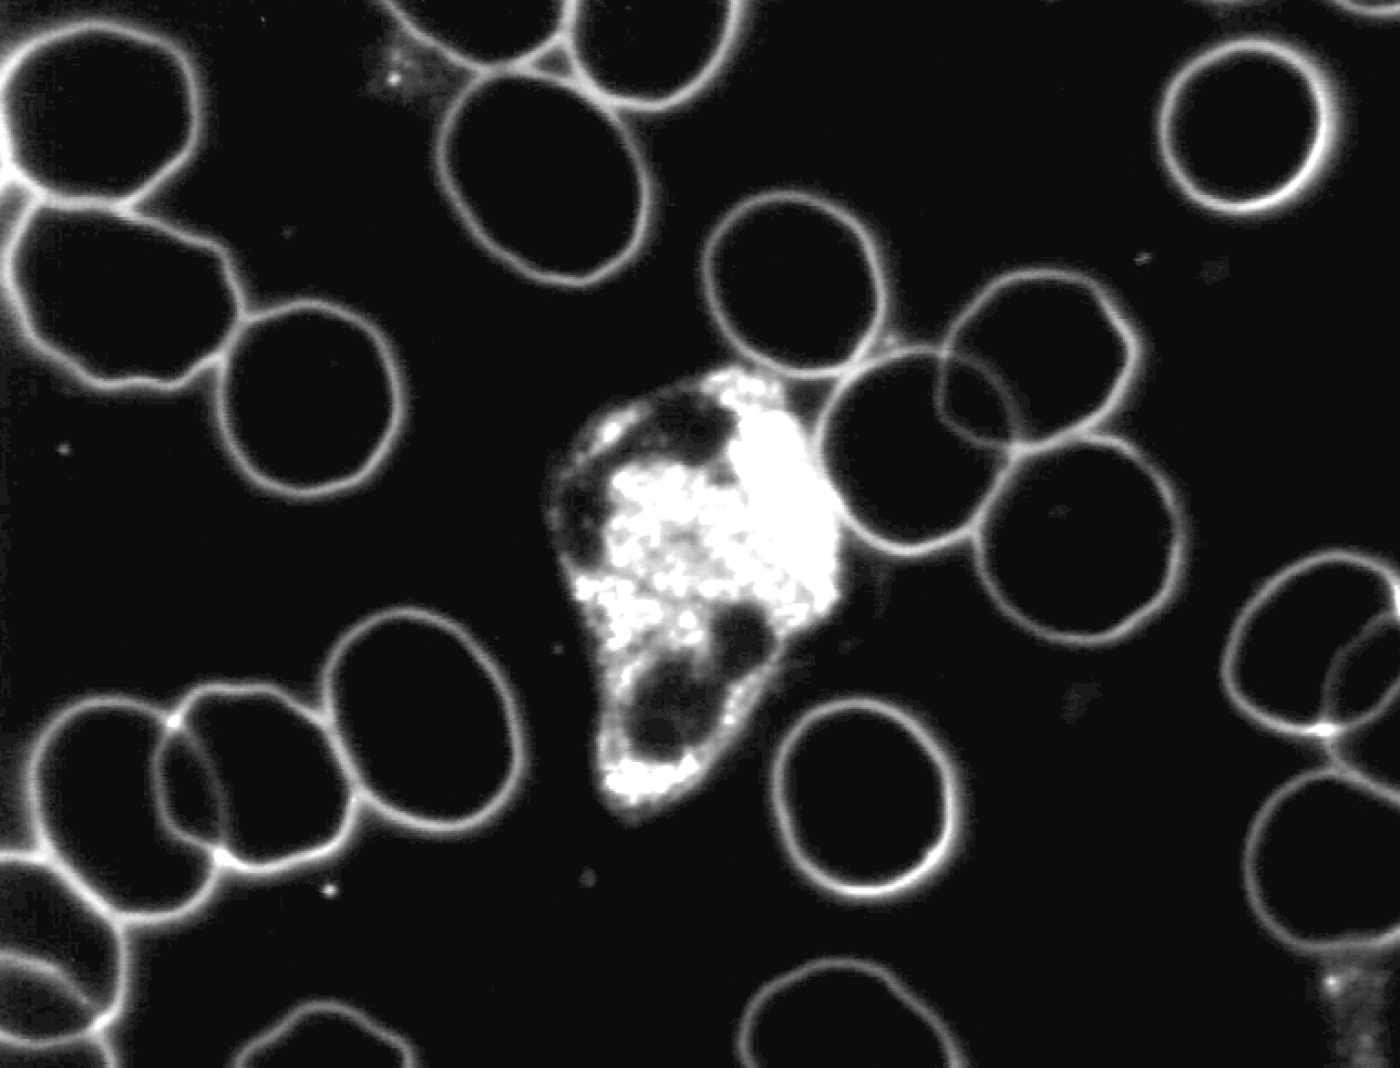

Na de neutralisatie vertonen de witte bloedlichaampjes (granulocyten) een verhoogde motiliteit en de intracellulaire activiteit neemt toe. De vorming van pseudopodieën treedt frequenter op. De witte bloedlichaampjes kunnen dan actief zijn in het afweersysteem.

Zie ook onderstaande foto’s met een karakteristiek beeld van vóór en na de neutralisatie met Benzoliet.

Levend bloedbeeld

na neutralisatie met Benzoliet

De witte bloedlichaampjes worden over een periode van een half uur steeds actiever totdat ze als super actief geclassificeerd kunnen worden. Deze verhoogde activiteit gaat gepaard met een verhoogde motiliteit, veelvormigheid en een verhoogde intracellulaire activiteit.

De veranderingen die werden geconstateerd na neutralisatie van de toegepaste verstorende subtiele energieën door Benzoliet in met name de witte cellen waren:

• toegenomen mobiliteit

• toegenomen en homogeen over de cel verspreide cytoplasmatische activiteit

• verlaten van de bolvorm

• het vormen van pseudopodieën

Hieruit volgt de conclusie dat Benzoliet in staat is de in de proef toegepaste verstorende subtiele energieën te neutraliseren en dat door neutralisatie het afweersysteem beter kan functioneren.